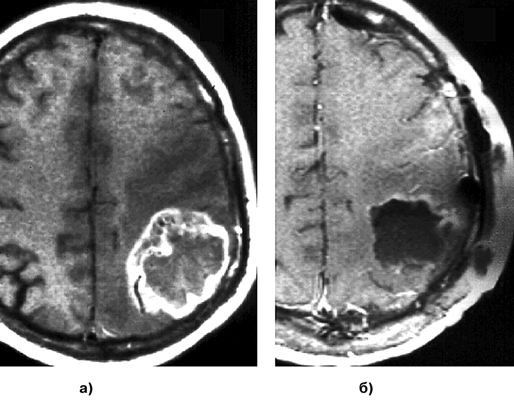

Как и при АА, опухолевые клетки ГБ могут быть обнаружены за пределами зоны усиления сигнала и перифокального отека, выявляемых при МРТ. ГБ широко и быстро распространяются по трактам белого вещества. Типично также распространение на противоположное полушарие через мозолистое тело, переднюю и заднюю комиссуры, реже вдоль внутренней и наружной капсул (рис. 5а, б, г). При полушарных ГБ иногда определяется распространение опухоли в ножки мозга и в заднюю черепную ямку.

Рисунок 5. Примеры роста и распространения глиобластомы (МРТ, Т1-взвешенные изображения с контрастным усилением, аксиальная проекция):

а — "передняя бабочка" — глиобластома медиальных отделов обеих лобных долей, больше слева и колена мозолистого тела; б — "задняя бабочка" — глиобластома медиальных отделов теменно-затылочных с обеих сторон, больше справа и валика мозолистого тела; в — первично-множественный рост глиобластомы; г — перивентрикулярное распространение глиобластомы, больше вокруг передних рогов обох боковых желудочков

В 5–10% всех случаев ГБ и ГС отмечается метастазирование в пределах ЦНС. ГБ имеет наихудший прогноз среди всех первичных опухолей ЦНС. Средняя продолжительность жизни не превышает 12 мес. Хотя некоторые авторы считают достаточной частичную резекцию этих агрессивно растущих инфильтративных опухолей, преобладает мнение о необходимости максимально возможного радикального удаления. Стандартным является применение адъювантной терапии в виде внешней лучевой терапии и химиотерапии, в основном на базе схем, использующих препараты нитрозомочевины. Средняя продолжительность жизни после удаления, удаления с последующим курсом лучевой терапии и после удаления с последующим курсом лучевой терапии и химиотерапии составляет в среднем 4, 9–10 и 10–12 мес соответственно. При применении агрессивной комбинированной мультимодальной химиотерапии, включающей последовательное применение различных сочетаний препаратов, повторных операций и внутритканевой лучевой терапии, показатель средней продолжительности жизни больных увеличивается до 12–15 мес. Менее 10% составляет 2-летняя выживаемость, а 5-летняя — около 2%. Более благоприятный прогноз у больных молодого возраста, с исходным удовлетворительным состоянием и при возможности радикального удаления опухоли (рис. 6а, б). Прогноз для больных старше 65 лет очень плохой.

Рисунок 6. МРТ, Т1-взвешенные изображения с контрастным усилением до (а) и после (б) удаления глиобластомы теменно-затылочной области слева. Пример радикального ("тотального") удаления — участков накопления контраста после операции не выявляется